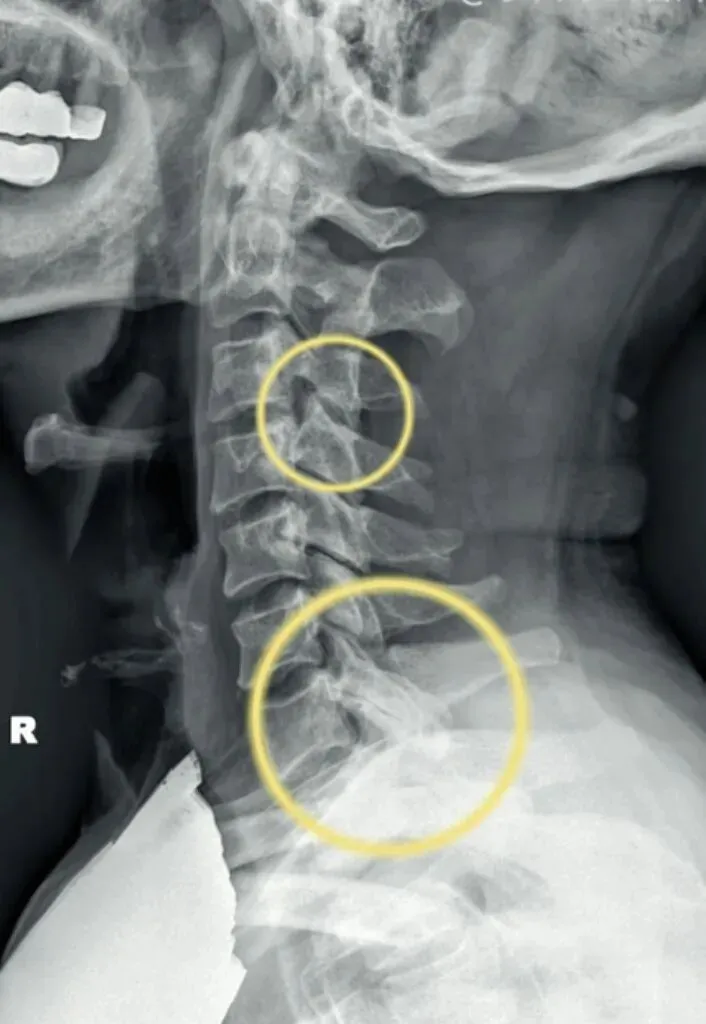

一骨是是我们主要在颈椎侧位X线片中观察椎体的形态与结构,查看椎体是否规则,

椎体边缘有无变尖或呈唇样改变的骨质增生。

椎体骨质有无破坏,密度是否正常,如肿瘤或者感染。

椎体的高度是否均匀,有无压缩变形。椎体高度减小可能提示骨质疏松、压缩性骨折

或椎体的发育异常等。